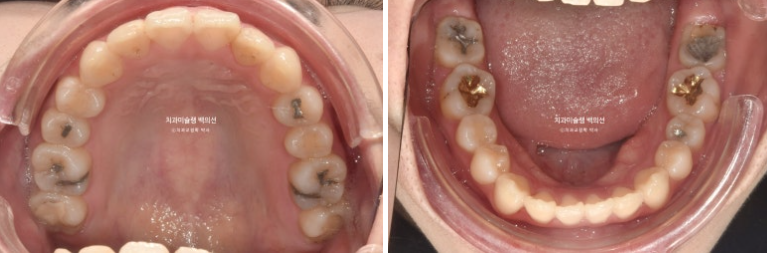

23년 7월 교정치료를 위해 내원한 20대 환자분입니다.

오래 전 비발치교정을 했던 이력이 있습니다.

앞니는 가지런한 편이며 중심선도 거의 맞습니다.

교합은 좋은 상태이고

치열도 꽤 가지러한 편입니다.

입안 사진만 보면 재교정을 왜하나 싶겠지만 환자분이 재교정을 해서라도 고치고 싶은 것은

돌출입

거미스마일 입니다.